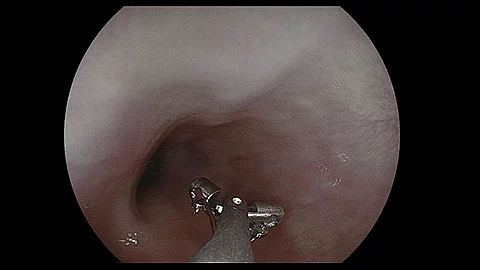

Endoskopisches LehrvideoPolyp im Divertikel

Unser neues Endoskopie-Video zeigt einen offensichtlichen Befund, der aber auch leicht zu übersehen ist. Welcher das ist und welche Methode zur Behandlung angewandt wurde, präsentiert PD Dr. Jochen Weigt vom Uniklinikum Magdeburg.